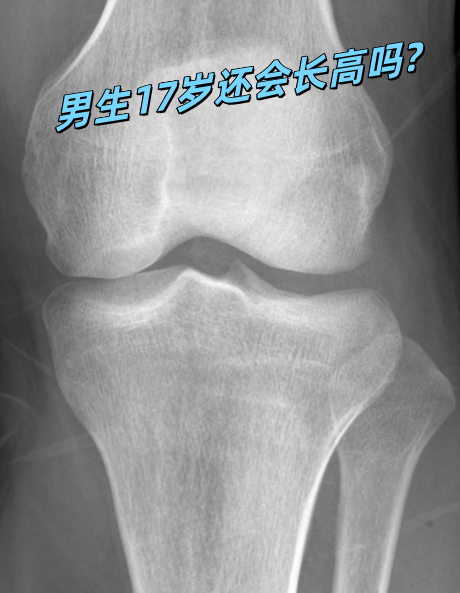

确定骨骺线状态的方法要确定骨骺线的状态,通常需要进行影像学检查,如X线片拍摄腕关节或膝关节的X线片,可以清晰地观察到骨骺线的状态如果X线片显示骨骺线还存在,那么女孩就有可能继续长高骨骺线已闭合如果17岁女孩的骨骺线已经闭合,那么她长高的可能性就非常小了骨骺线闭合意味着骨骼生长的。

判断方法要确定自己是否还能长高,最准确的方法是进行骨骼年龄检测,通过X光片观察骺软骨的状态如果骺软骨已经闭合,那么自然长高的可能性就非常小了综上所述,17岁后能否长高主要取决于个人的骺软骨是否已经完全闭合如果仍有生长空间,可以通过合理的饮食适量的运动和良好的生活习惯来促进身高增长。